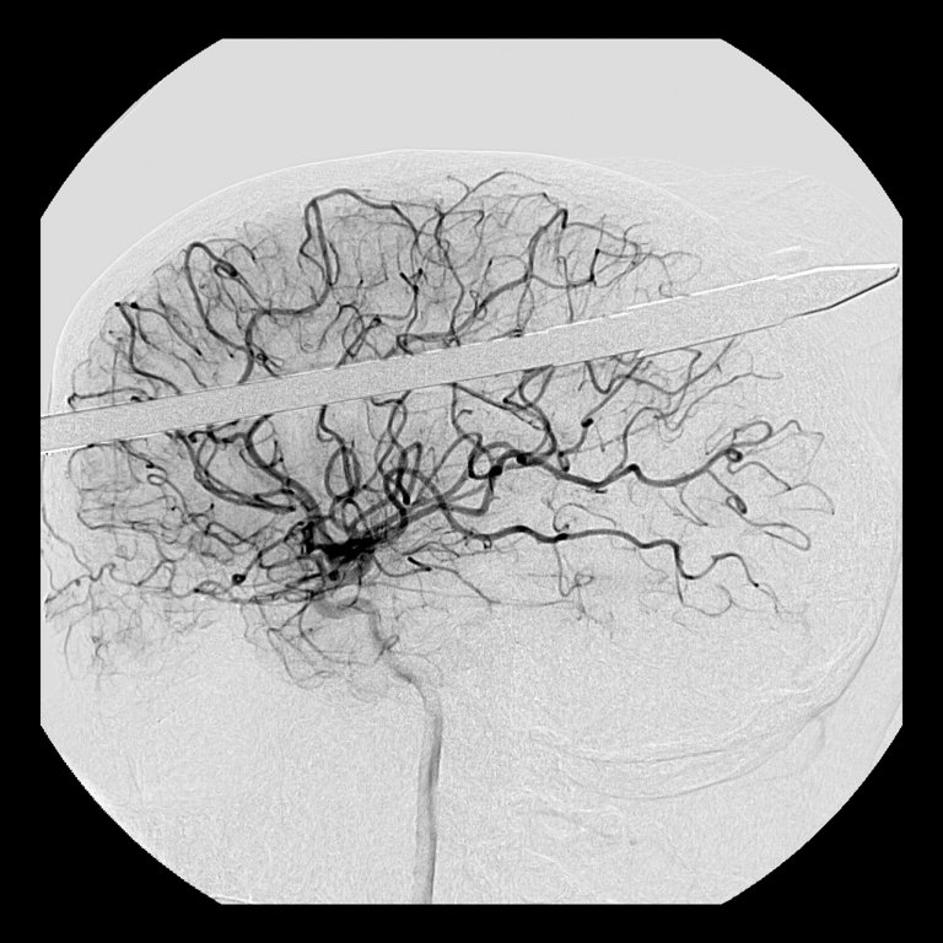

Glavo mu je preluknjala harpuna